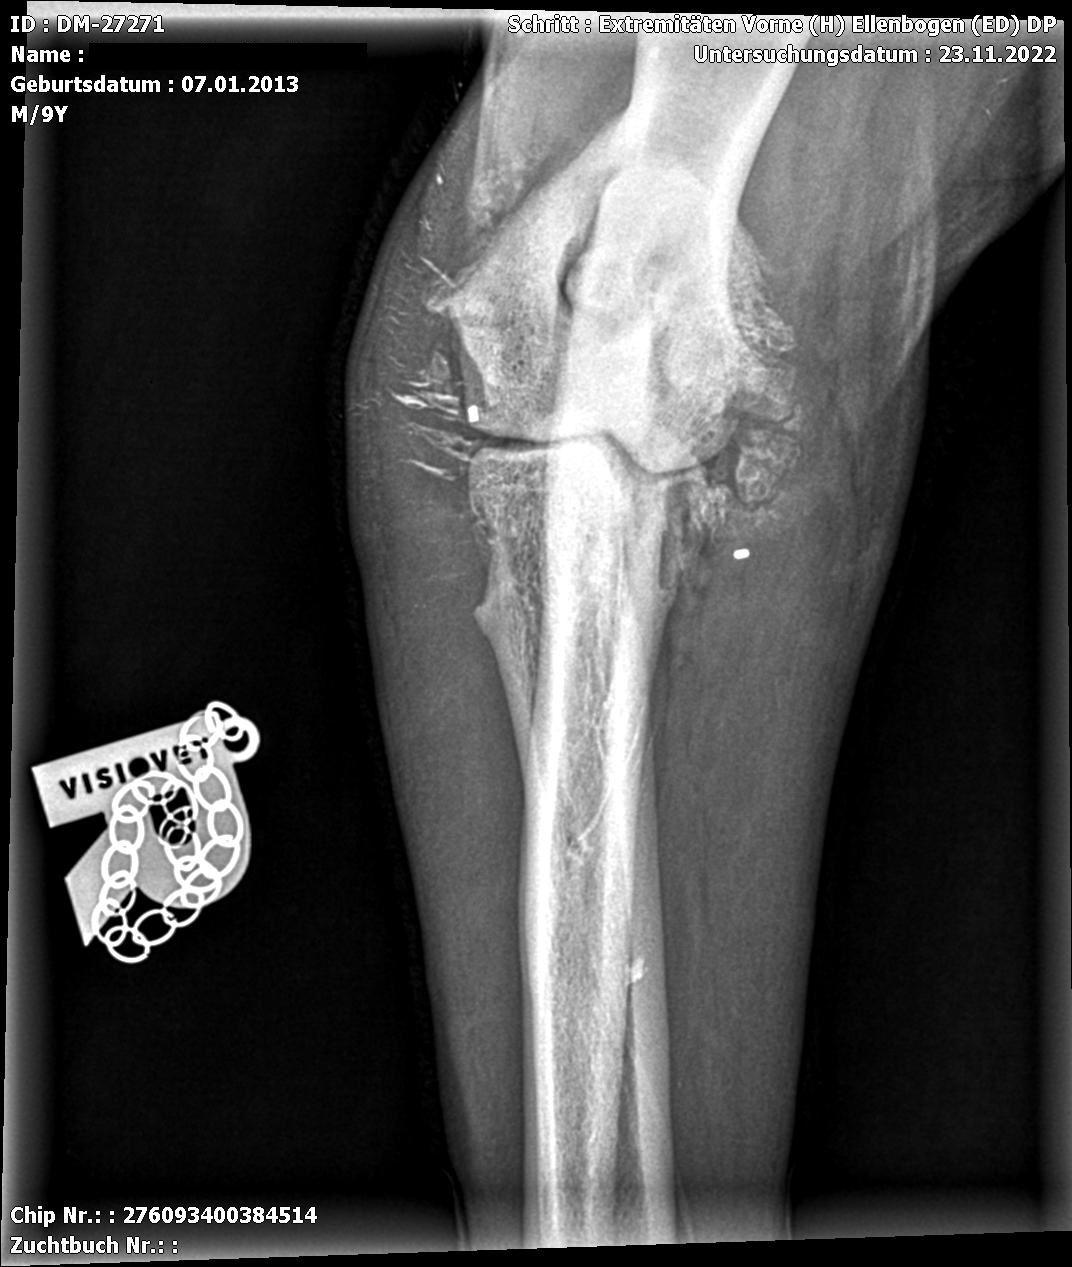

Die Ellbogendysplasie ist die häufigste Entwicklungsstörung des Ellbogengelenks bei juvenilen und erwachsenen Hunden mittelgroßer und großer Rassen und verursacht oftmals eine Lahmheit der Vordergliedmaßen. Viele Rassen (Labradore etwa) haben eine genetische Veranlagung, eine Ellenbogengelenksdysplasie zu entwickeln.

Diese Erkrankungen können sich isoliert oder in Kombination präsentieren. Jede Form der Ellbogendysplasie kann eine irreversible Osteoarthrose (OA) des Gelenks durch Knochen- und Knorpelläsionen, Instabilität und chronische Synovitis hervorrufen. Die Ellbogendysplasie des Hundes wird als eine polygenetische Erkrankung beurteilt, wobei Umgebungsfaktoren und genetische Faktoren bei der Entwicklung der Läsionen eine entscheidende Rolle spielen

Die Coronoiderkrankung ist die am häufigsten vorkommende Form des Ellbogendysplasie-Komplexes. Die Symptome können initial subklinisch sein, sich aber auf Dauer als deutliche Lahmheit manifestieren. Die Coronoiderkrankung ist, wie viele Gelenksläsionen, durch eine progressive Osteoarthrose charakterisiert.

Eine gründliche Diagnostik hilft die Erkrankung zu diagnostizieren und die Schädigung des Gelenkes umfassend zu analysieren. Hier hilft uns unser CT und die Arthroskopie. Zur abschließenden Diagnostik und vor allem Therapie hat sich die Arthroskopie international als Goldstandard durchgesetzt. Sie ermöglicht eine direkte Beurteilung von Knochen und Gelenkknorpel. Wir operieren bereits seit 2004 Gelenke arthroskopisch.